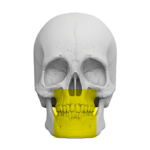

Zakres pracy tomografu.

(Badanie CBCT)

Żuchwa ( 10 cm x 5 cm )

Szczęka i żuchwa

( 12 cm x 10 cm )